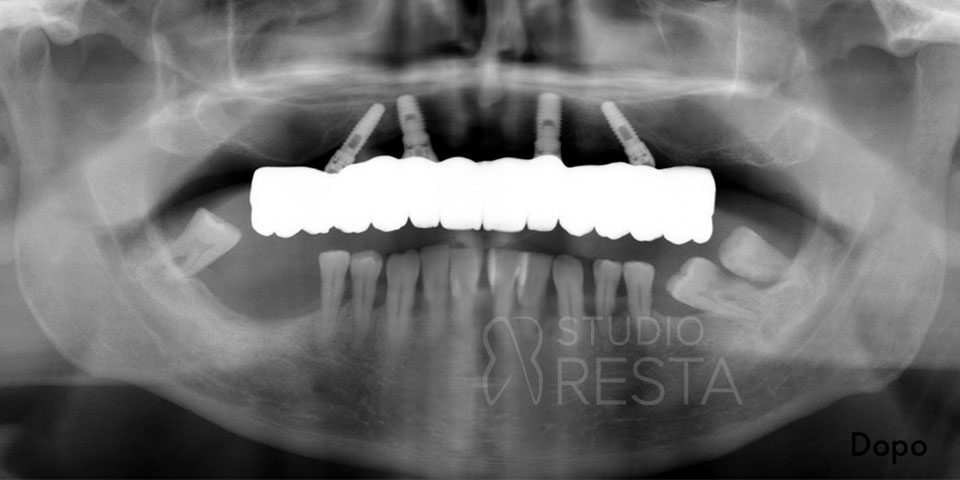

- Controllo radiografico finale: a completamento dell’intervento, eseguiamo una radiografia di controllo (OPT) per verificare l’esatto posizionamento dei quattro impianti. Spesso si noterà che i due impianti posteriori sono inclinati verso la parte posteriore dell’arcata (tilted implants), confermando il caratteristico assetto “a V rovesciata” dell’All on 4.

All on Four Senza Gengiva Finta

L’implantologia All on Four senza gengiva finta è un’opzione protesica che non prevede l’utilizzo sulle protesi dentali di gengiva artificiale. Questo approccio consente un’estetica migliore e soprattutto un aspetto più naturale delle protesi in modo da renderle perfettamente mimetizzabili.